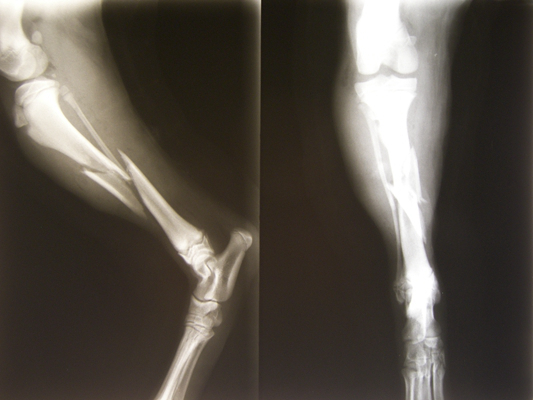

骨折圖片